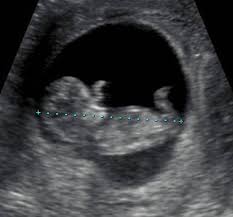

It's used to see how far along in your pregnancy you are and check your baby's development. The dating scan usually takes about 20 minutes. Purpose of the pregnancy dating scan. This is because the scan measures the size of your baby. The dating scan can include a nuchal translucency (nt) scan, which is part of the combined screening. This is an ultrasound scan that is performed early in the pregnancy. Nearly all scans after 10 weeks can be done through your tummy, and most units ask you to arrive with a full bladder. Continue to look at their picture until you find one attractive feature. A dating scan is an ultrasound scan to determine how many weeks pregnant you are and your due date. Listen, i don't want to say that dating includes having sex. #4 it can include sex. This gives the most accurate estimation of the baby's age, based on development. The clerk of usps scans the bar code of the mail and updates the status of the package at the usps system, then sends it to its next destination.

The phrase 'dating' is extremely common, and so is the grey area that tends to follow it around. A dating scan might be recommended before 12 weeks to confirm your due date if you are unsure of your last menstrual period or your date of conception. What does awaiting delivery scan mean? In some cases, it is also done after 21 weeks. When i went for my dating scan, at 12+6, the sonography didnt say anything to me about my baby, she just said i was around 13weeks. The earlier a dating ultrasound is done, the more accurate the estimated due date is. A difference in age in your first trimester could indicate two things:. Dating scans during pregnancy | june 2018 this written information is for guidance only and does not replace consultation and advice by your health care provider.

It checks if the fetus is growing normally and has any congenital abnormalities. I will keep you posted on how things go, thanks again smile. If it has implanted outside your uterus, it's called an ectopic pregnancy, which is a medical emergency. Other information obtained includes whether the pregnancy is in the uterus or outside the uterus (an ectopic pregnancy), how many embryos there are, and. Though 28 days is called average, 32 days is closer to average length. Posted tuesday 04 december 10:51am. This is an ultrasound scan that is performed early in the pregnancy. A dating scan is in fact more accurate the earlier it is done. 'is a scan that uses sound waves to create a picture. When i went for my dating scan, at 12+6, the sonography didnt say anything to me about my baby, she just said i was around 13weeks. You know, catch a glimpse of who they are. It is also known as a 'anomaly scan' or an '18 to 20 week scan'. During a dating scan, your sonographer will also check that the embryo has implanted in your uterus (womb).

During a dating scan, your sonographer will also check that the embryo has implanted in your uterus (womb). In the states the most accurate way to date a pregnancy is with an ultrasound done between 6 weeks and 8 weeks, 6 days, according to dr. #4 it can include sex. This does not mean there is. Your midwife or doctor will book you a dating scan appointment.